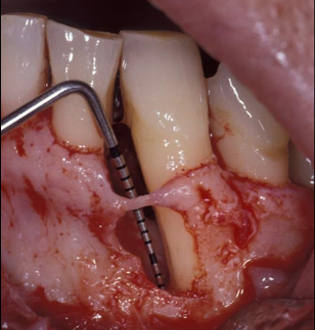

ポケットの深さは15㎜ありました。

レントゲンでは根尖(根の先端)付近まで骨吸収が認められます。

(手術中の写真)

レントゲンと一致して深い骨欠損が認められます、根の表面の汚れを取り除きました